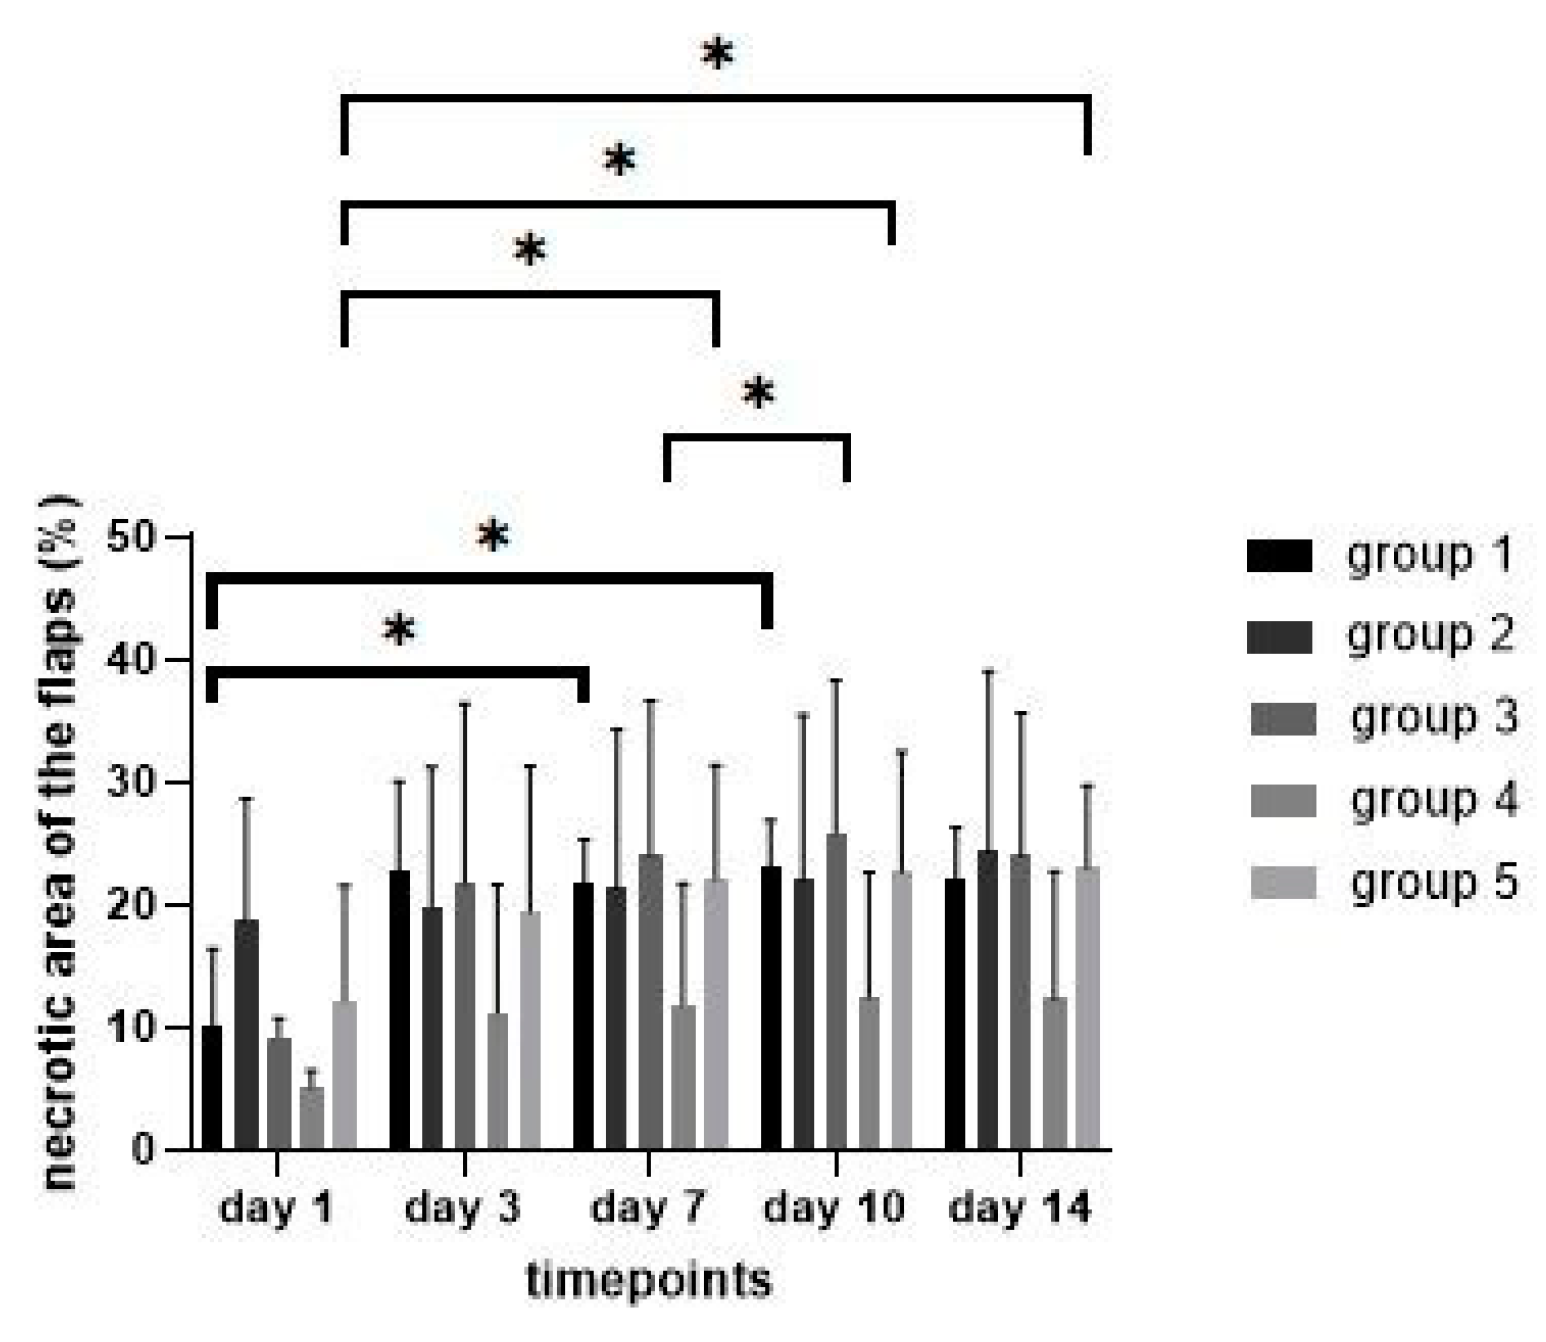

3.2. Necrotic Areas of Flaps